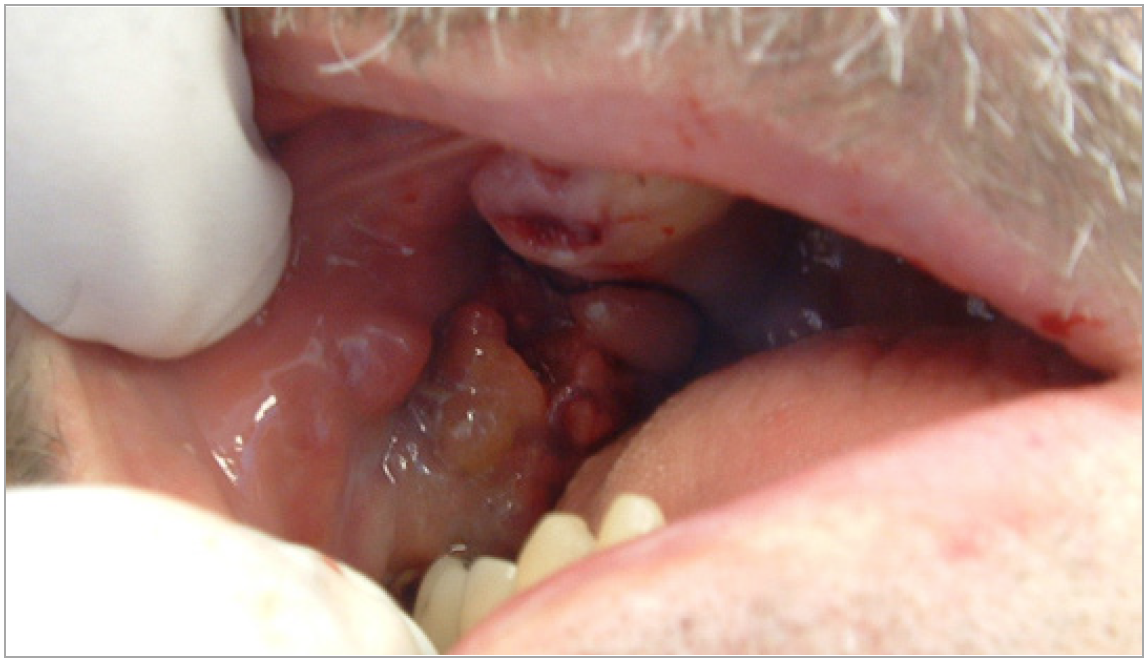

Figure 2. Example of Oral Cancer - courtesy of dentalcare.com

Figure 2

Patients typically present with a sore throat, ear pain, painful swallowing, or hoarseness, and on physical exam they often have lymph node involvement in the neck. The highest risk sites are at the base of the tongue and the tonsillar area. Palpation of the neck has never been more important. The highest frequency of HPV-positive cancer is related to oral sex and to the number of partners. Figure 2 shows an example of cancer, found on the buccal mucosa.